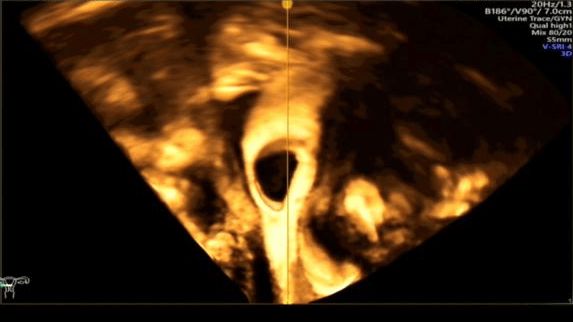

正常清晰显示双侧宫颈及输卵管

正常双侧卵巢周围造影剂呈环形包绕